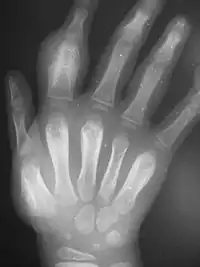

Secondary yaws affects the skin and bones.[13] The most common bone-related problem is periostitis, an inflammation around the bone, often occurs in the bones of the fingers and the long bones of the lower arms and legs, causing swollen fingers and limbs.[13] This causes pain at night and thickening of the affected bones (periostitis).[2] About 75% of infected children surveyed in Papua New Guinea reported joint pain.[2] Swollen lymph nodes, fever, and malaise are also common.[13]